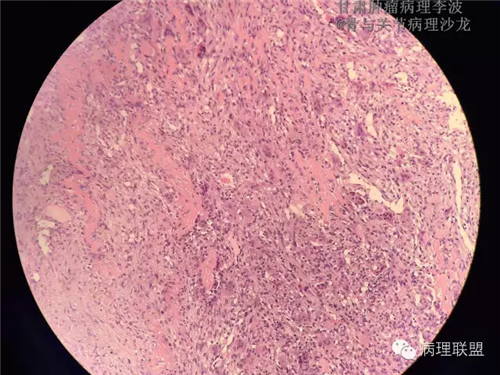

M/14 骶骨骨肉瘤-张惠箴讲解

病例由甘肃肿瘤病理 李波 提供,致谢。